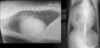

Q

What is shown in these images?

A

patent ductus arteriosus

-LVE and LAE

-normal to large pulmonary vessels

-triple bump sign